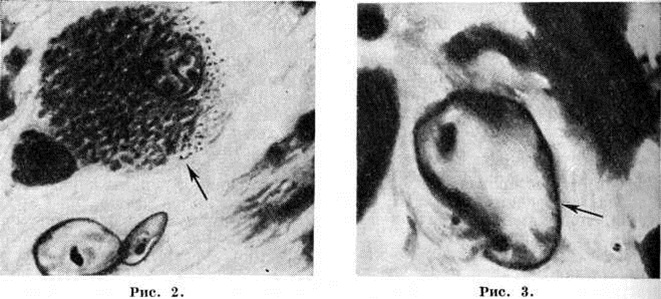

Рис. 2. и 3.

Микропрепараты головного мозга больного, умершего от гепато-церебральной дистрофии: рисунок 2 — клетка первого типа глии Альцгеймера (клетка с большим телом) — указана стрелкой; рисунок 3 — клетка второго типа глии Альцгеймера, лишённая цитоплазмы и состоящая из одного большого ядра — указана стрелкой.